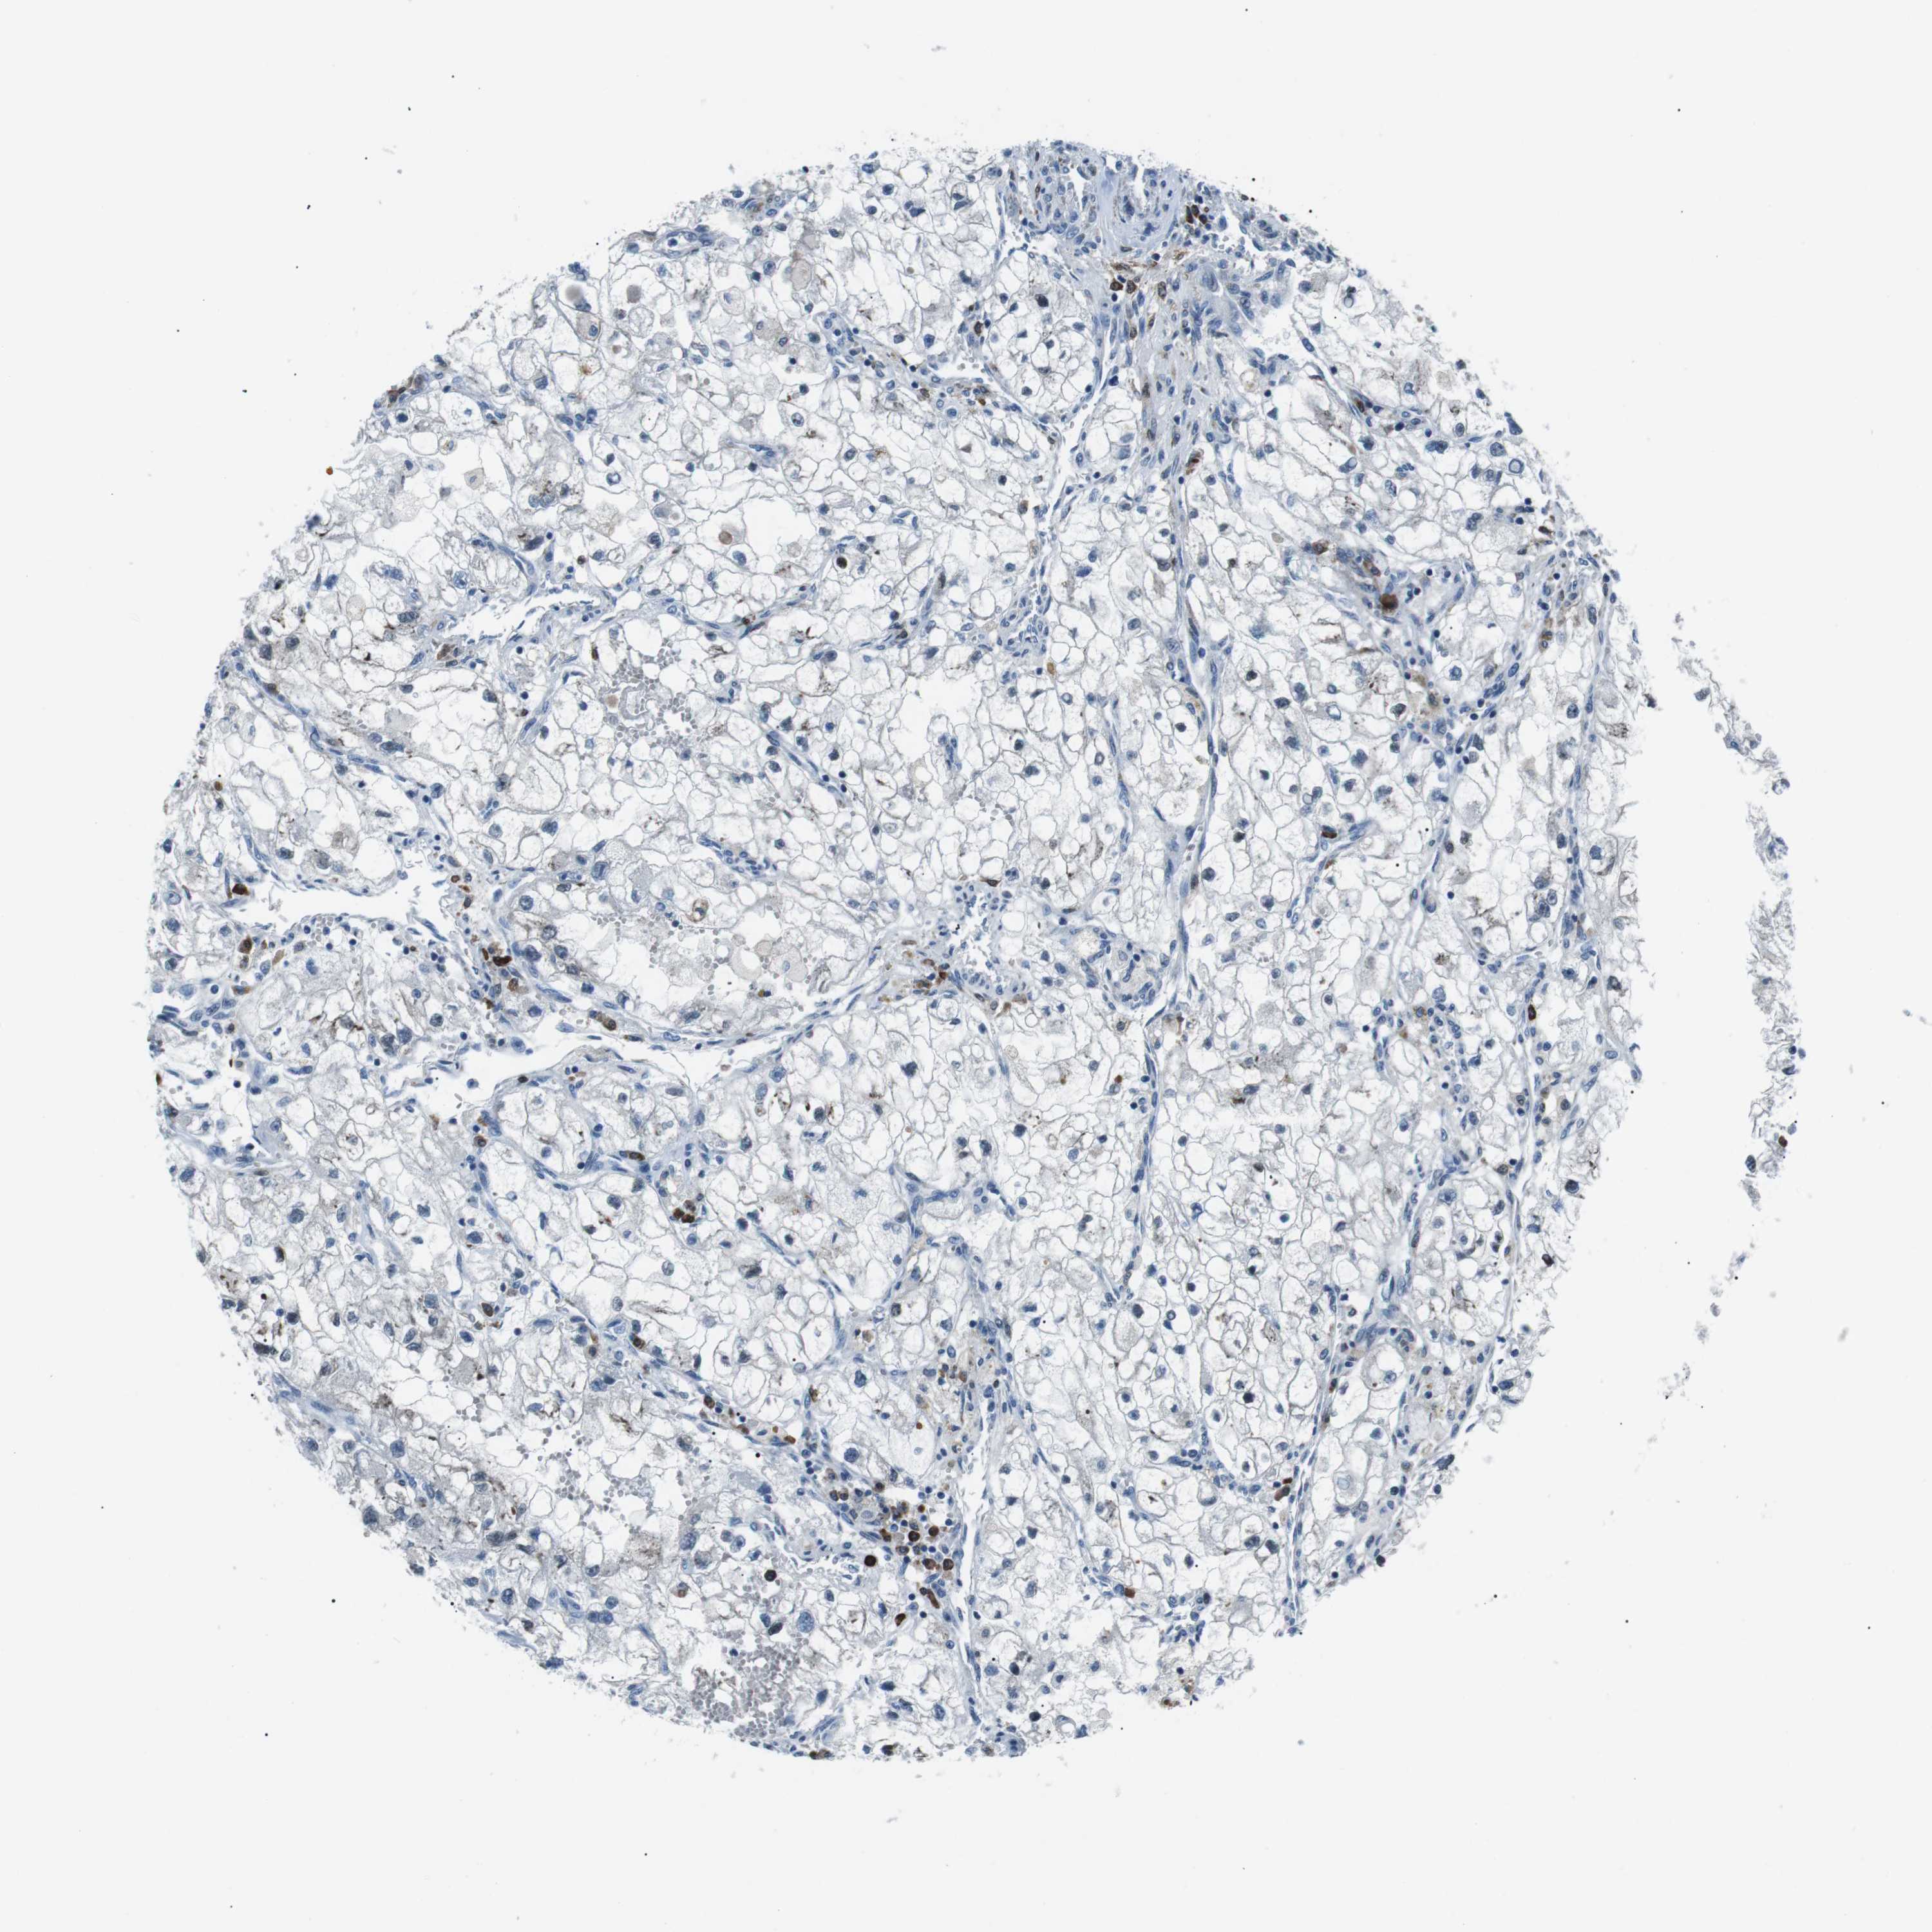

CANCER RENAL CANCER Show tissue menu

KICH TCGA KIRC TCGA KIRC VALIDATION KIRP TCGA PROTEIN RCC CPTAC PROTEIN EXPRESSION